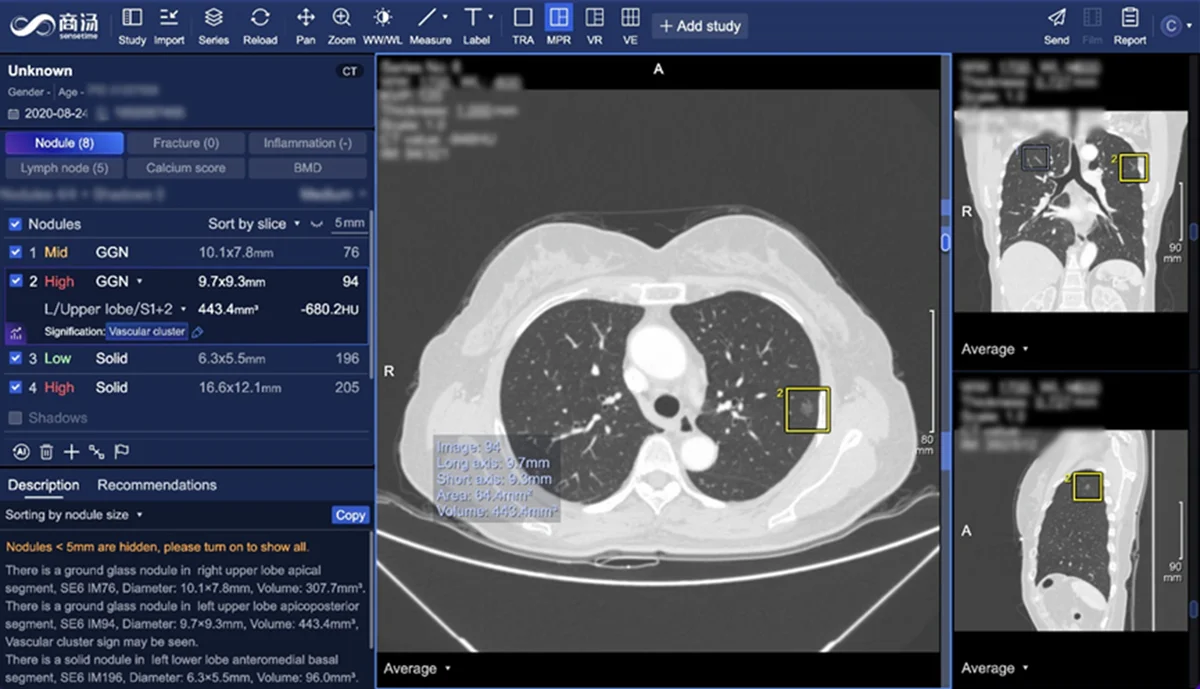

商湯SenseCare®系統於新加坡IHH醫療集團旗下百匯放射科正式上線(圖源:百匯放射科)

東南亞地區肺癌的早期發現率偏低,這使得高效且精準的篩查工具成為當務之急。基於深度學習的AI影像分析技術(即利用人工智慧處理醫學影像的技術)可在短時間內識別CT影像中僅幾毫米大小的肺結節,並智能提示潛在風險。在此基礎上,該系統還具備自動對比不同時間點影像數據的功能,進一步追蹤病灶變化,協助醫生進行數字化的病情評估。此技術大幅提升篩查效率,並降低漏診率,為患者提供更可靠的健康管理方案。